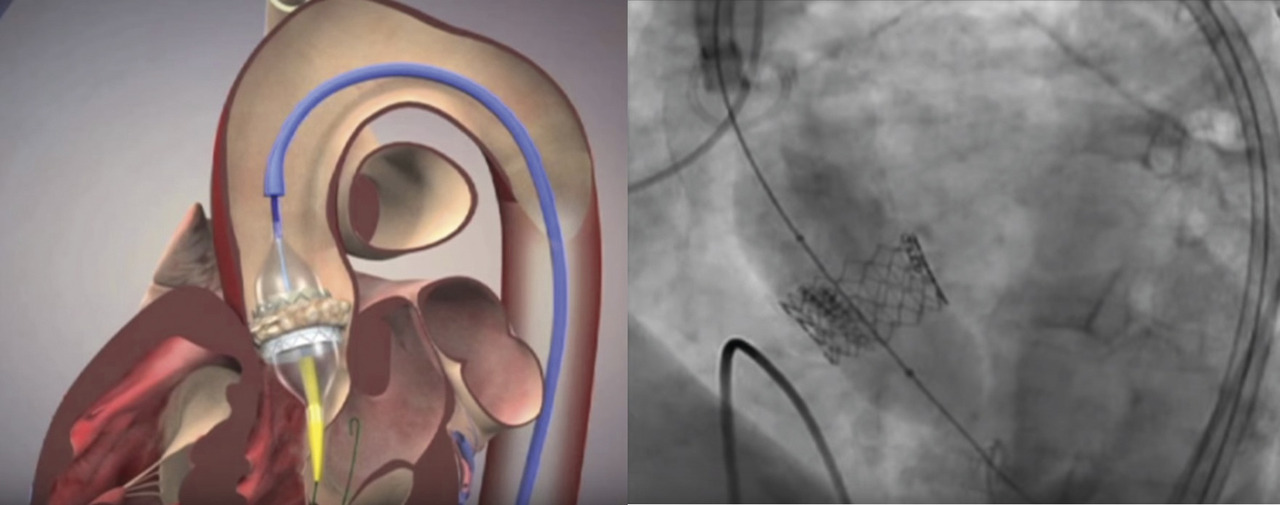

Chez les plus de 75-80 ans et les sujets ayant un thorax « hostile » en raison d’un antécédent de radiothérapie ou de chirurgie cardiaque, ou dont le risque opératoire (EuroSCORE II ou score STS) est intermédiaire ou élevé, l’implantation d’une bioprothèse par voie percutanée (TransArterial Valve Implantation, TAVI) est désormais préférée (fig. 3).2, 4 Elle est supérieure en termes de survie au traitement médical chez les patients inopérables et a des résultats comparables à la chirurgie chez les malades à risque intermédiaire ou élevé.5-8

Même si cette procédure est moins lourde par rapport à une thoracotomie sous CEC, elle est accompagnée d’une morbidité non négligeable : risque d’AVC embolique, nécessité d’implantation de stimulateurs cardiaques après la procédure, hémopéricarde, complications vasculaires, rénales, endocardite sur prothèse, complications des angioplasties coronaires réalisées avant le TAVI… à noter que l'éradication des foyers infectieux extracardiaques s’impose de la même façon qu’avant remplacement chirurgical. De plus, le recul sur la durabilité de ces prothèses montées sur un stent est encore limité (5 ans au maximum, études menées chez des sujets très âgés à haut risque et taux de mortalité élevé) pour généraliser leur implantation chez des sujets à faible risque dont l’espérance de vie est élevée.